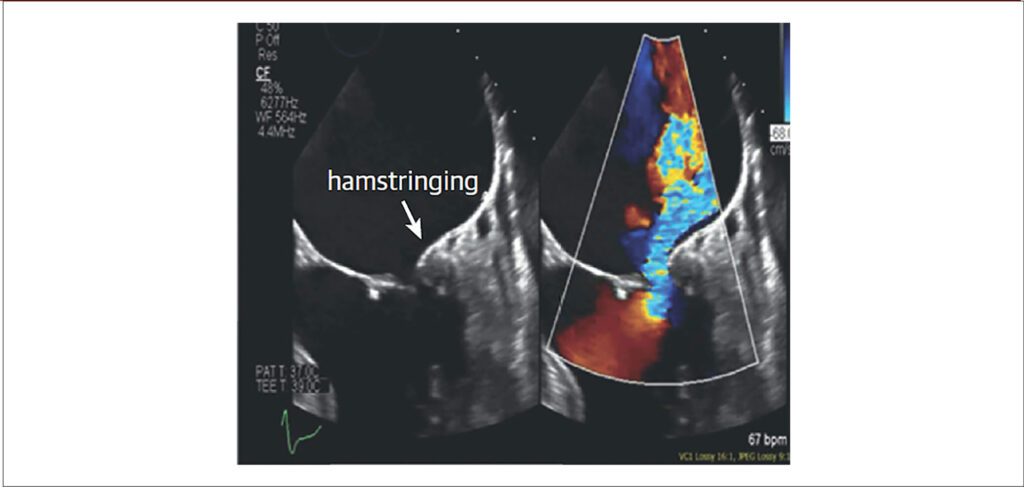

A insuficiência mitral (IM) secundária no cenário da doença ventricular sempre frequentou a pauta dos congressos e atingiu amplo conhecimento fisiopatológico ao longo dos anos. Mais recentemente, com incidência crescente de fibrilação atrial (FA) e de insuficiência cardíaca com fração de ejeção preservada (ICFEP), um novo fenótipo até então pouco comentado veio à tona: a IM funcional atrial (IMFA). Nessa entidade, a atenção especial deve ser direcionada ao átrio esquerdo e ao anel mitral, visto que em fases precoces cursam com dimensões e função ventricular esquerda normais.